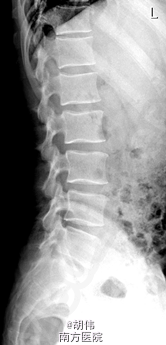

腰椎间盘突出症 (L4/5)

主诉:腰痛半年,右下肢放射痛一月。 病史:男性患者,45岁。患者半年前在打球时不慎跌倒,出现腰部疼痛,自行敷药,疼痛缓解后未进行后续治疗。自觉久坐后腰酸痛明显,一月前腰部疼痛加重,伴右下肢放射痛,没有麻木感。疼痛在运动后尤为明显,休息后可稍缓解。患者一般情况尚可。

查体:脊柱生理弯曲存在,无明显侧后凸畸形。腰4/5、腰5/骶1棘间及左右棘旁轻度压痛,余棘突及棘间无明显压痛及叩击痛。右侧坐骨神经出口处有轻压痛。右侧大腿前侧,小腿外侧感觉减退,余四肢感觉、肌力无明显异常。双侧膝踝反射无亢进或减弱,双侧踝阵挛、踝阵挛阴性。双侧Babinski 征及Oppenheim 征(-)。双侧直腿抬高试验(-),加强(-)。 辅助检查:主要影像学检查请查阅下列图片。

诊断:腰椎间盘突出症 (L4/5)。 处理:入院后给予对症治疗,完善相关检查,做好术前评估,暂行手术:内镜通道下L4/5椎间盘摘除+ Cage植骨内固定。